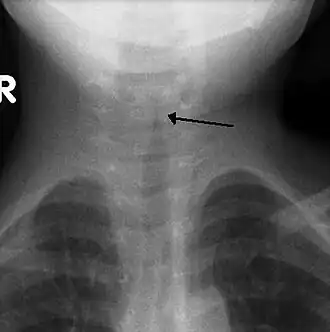

Usualmente no se realiza una radiografía frontal del cuello,[4] pero si se hace, puede mostrar un estrechamiento característico de la tráquea, llamado signo de punta de lápiz o del campanario, debido a que la estenosis subglótica tiene forma de un campanario. El signo del campanario sugiere el diagnóstico, pero está ausente en la mitad de los casos.[3]